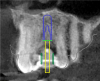

The CBCT and digital scan were placed in software to merge the two. Figure 8 shows the superimposition of the scan over the CBCT. The clinician used the volumetric data to determine implant size, depth, and position. The surgeon, dentist, and laboratory were all involved in a conference call to go through several different implants. They chose the implant size and length based on the position of the sinus, the width of the alveolus, and the appropriate position for an ideal surgical result.

Fig 8. Superimposition of digital scan over the CBCT.

Figure 8